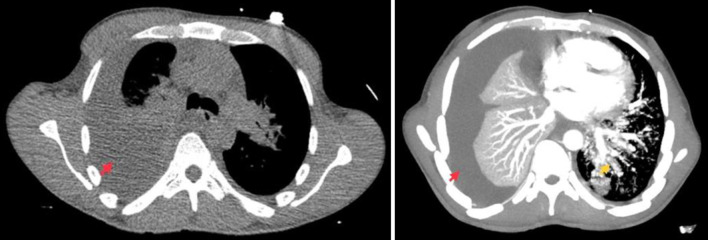

卡波西肉瘤(KS)是一种影响皮肤和淋巴结的血管增生性肿瘤。人类疱疹病毒-8(HHV-8)会感染血管内皮,并通过产生血管内皮生长因子和细胞因子诱导血管生成,从而引发 KS。KS 的特征是皮肤和粘膜出现紫斑或色素沉着斑,内脏受累非常罕见。肺部 KS(PKS)是一种极为罕见的 KS 内脏表现,预后较差。PKS 常表现为咳嗽、咯血、胸膜炎性胸痛、发热和体重减轻。在本系列病例中,我们分享了诊断和治疗两名 PKS 患者的经验。我们还简要回顾了这种罕见疾病的流行病学、症状和体征、诊断和治疗。

Kaposi sarcoma (KS) is an angioproliferative neoplasm that affects the skin and lymph nodes. Human herpesvirus-8 (HHV-8) triggers KS by infecting the endothelium and inducing angiogenesis through the production of vascular endothelial growth factors and cytokines. KS is characterized by purplish or hyperpigmented plaques involving the skin and mucous membranes, and visceral involvement is very rare. Pulmonary KS (PKS) is an exceedingly rare visceral manifestation of KS and has a poor prognosis. PKS often presents with cough, hemoptysis, pleuritic chest pain, fever, and weight loss. In this case series, we share our experience in diagnosing and treating two patients with PKS. We also provide a concise review of the epidemiology, signs and symptoms, diagnosis, and management of this rare condition.